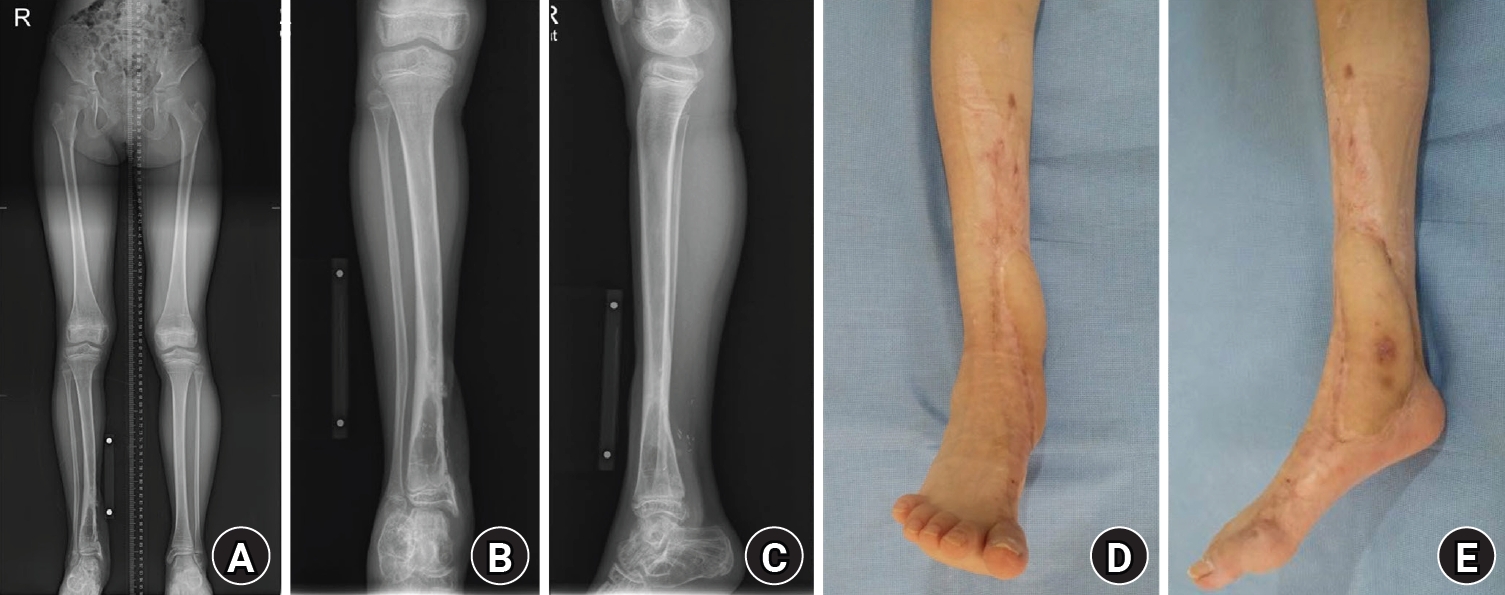

At the final follow-up on March 6, 2025, clinical photographs and radiographs demonstrated healed soft tissue, maintained alignment, and functional recovery without recurrent deformity (Fig. 8). Limb-length discrepancy was 5 mm. Active ankle dorsiflexion was 0° with passive dorsiflexion of 5°. The patient reported no pain and returned to unrestricted activities of daily living, including hiking and dancing. Complications during the treatment course were limited to superficial skin/soft-tissue problems, without reported deep infection (Table 1).

Fig. 8.

Final follow-up on March 6, 2025. (A) Orthoroentgenogram radiograph obtained at the final follow-up, demonstrating maintained overall alignment. (B) Anteroposterior radiograph of the right ankle obtained at the final follow-up, showing osseous healing and maintained alignment. (C) Lateral radiograph of the right ankle obtained at the final follow-up. (D) Anteroposterior clinical photograph obtained at the final follow-up, demonstrating healed soft tissue and maintained alignment. (E) Lateral clinical photograph obtained at the final follow-up, demonstrating healed soft tissue and functional recovery.

Fig. 8. Final follow-up on March 6, 2025. (A) Orthoroentgenogram radiograph obtained at the final follow-up, demonstrating maintained overall alignment. (B) Anteroposterior radiograph of the right ankle obtained at the final follow-up, showing osseous healing and maintained alignment. (C) Lateral radiograph of the right ankle obtained at the final follow-up. (D) Anteroposterior clinical photograph obtained at the final follow-up, demonstrating healed soft tissue and maintained alignment. (E) Lateral clinical photograph obtained at the final follow-up, demonstrating healed soft tissue and functional recovery.